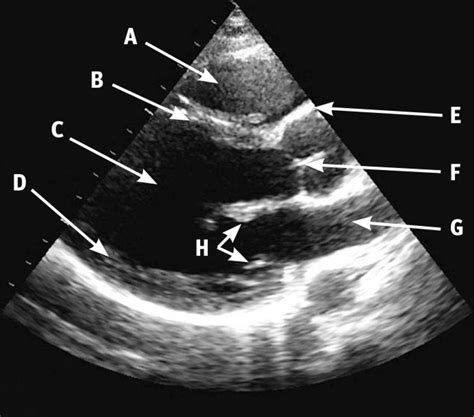

The Parasternal Long Axis view is obtained by placing the ultrasound probe in the parasternal position, which is the area just to the left of the sternum. The probe is oriented to capture a longitudinal section of the heart, providing a clear view of the heart's left side. This view is essential for evaluating the heart's anatomy and function, as it allows clinicians to assess the following structures:

• Left ventricle

• Left atrium

• Mitral valve

• Aortic valve

• Interventricular septum

• Aortic root

By examining these structures, clinicians can identify various cardiac abnormalities, including valve dysfunction, ventricular hypertrophy, and chamber enlargement.